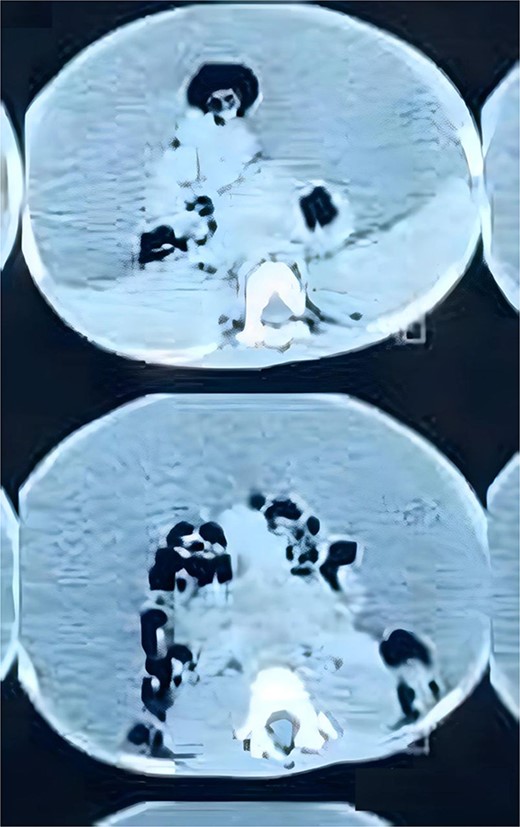

His complete blood count, serum electrolytes, renal and liver function tests were within normal range. A large cystic multiloculated abdominoscrotal lesion was highlighted in the abdominal ultrasound. The abdomen and pelvis CT with contrast showed a huge hypodense cystic lesion around 25x30 cm with hyperdense multiple internal septations without solid component causing compression and posterior displacement of bowel loops (Fig. 3). It extended through the left inguinal canal into scrotum (Fig. 4). The patient was referred to the pediatric surgery department for reassessment. Subsequently, the decision was made to go for excision.

Axial view of CT abdomen and pelvis demonstrates the cystic lesion entrapping the bowel loops centrally